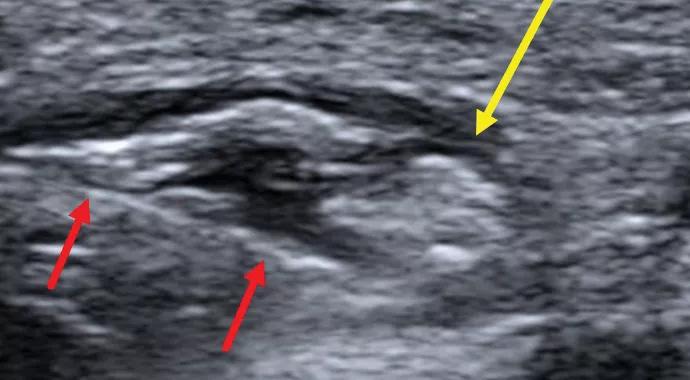

Conservative management — including NSAIDs, splinting and physical/occupational therapy — failed to relieve the patient’s symptoms, so he elected to undergo an ultrasound-guided perineural steroid hydrodissection (Figure 2). After one month, the patient reported a 75 percent subjective improvement in symptoms with only mild modification of activity.

Figure2. Transverse sonographic image demonstrating perineural hydrodissection with a 25-gauge needle (red arrows) of the superficial branch of the radial nerve (yellow arrow).